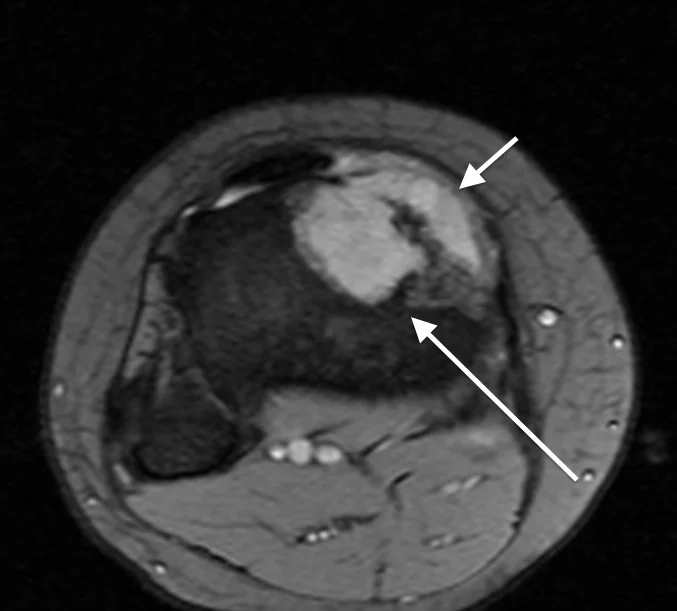

This 17 year old girl presented with several months of gradually worsening knee pain. The first image is the initial X-ray where there is subtle increased density inside the top portion of the tibia (arrows). The second image is the initial MRI, where the tumor is more obvious, replacing the marrow (long arrow) and also breaking out of the bone (short arrow). Image guided biopsy confirmed osteosarcoma. CT scans of her lungs and other studies showed the tumor was localized to the bone only (Stage IIa). The patient then started chemotherapy and about 3 months later was ready for surgery.